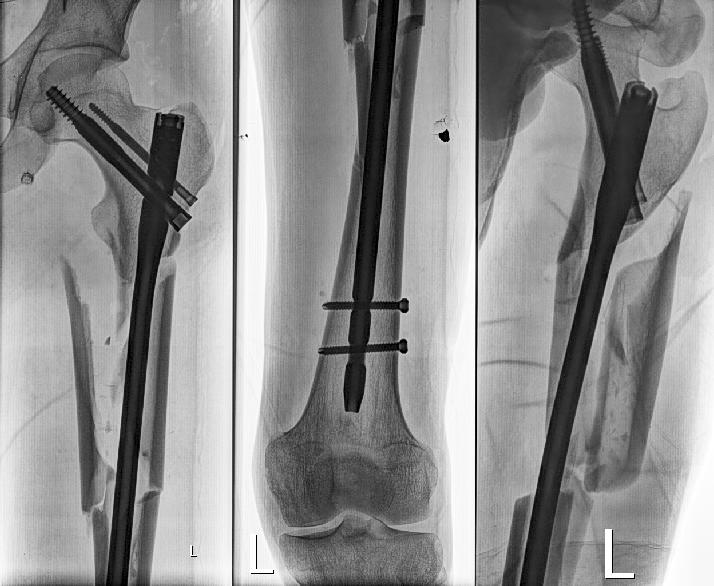

к примеру такой:

|